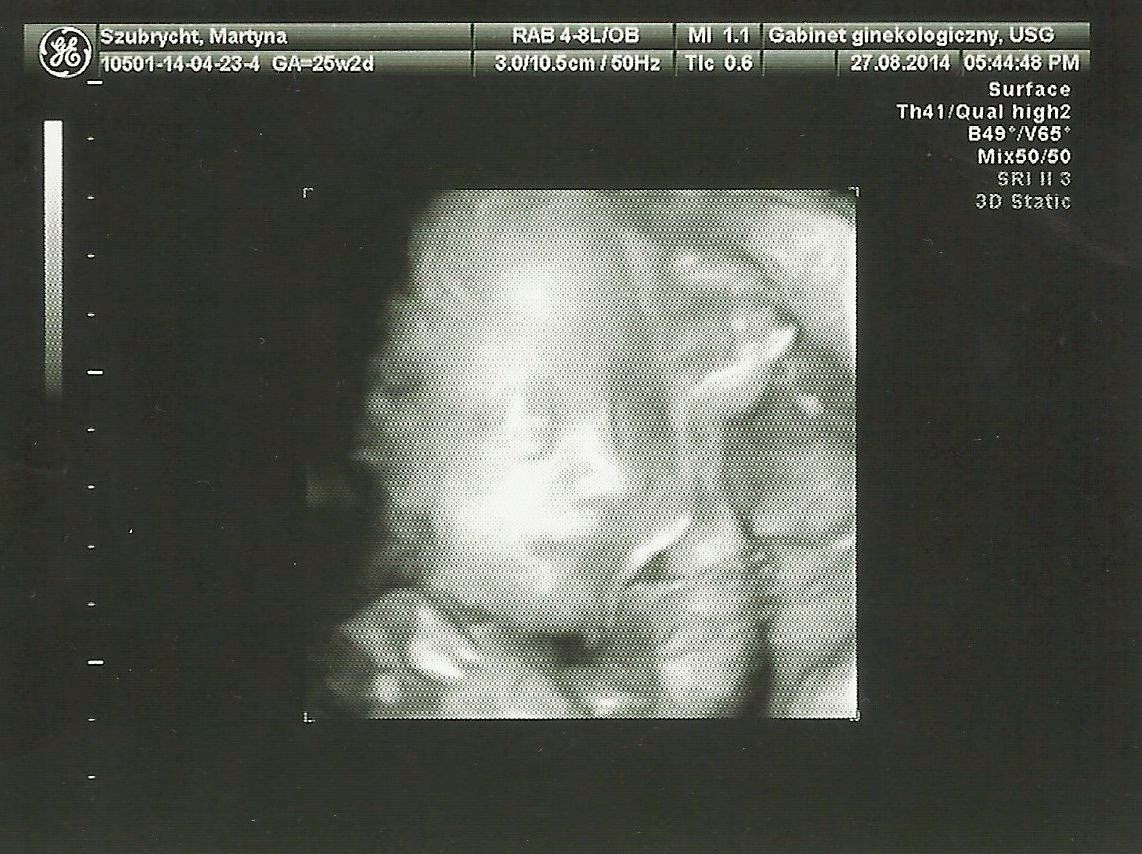

Przedstawiam Wam zatem Polę.

No i jak można było pomylić mojego Aniołka z chłopcem?! ;)

Jak się ładnie uśmiecha :) Jak to moja pani doktor ujęła, patrząc na takie foto, widać po twarzy, że dziewczynka :)